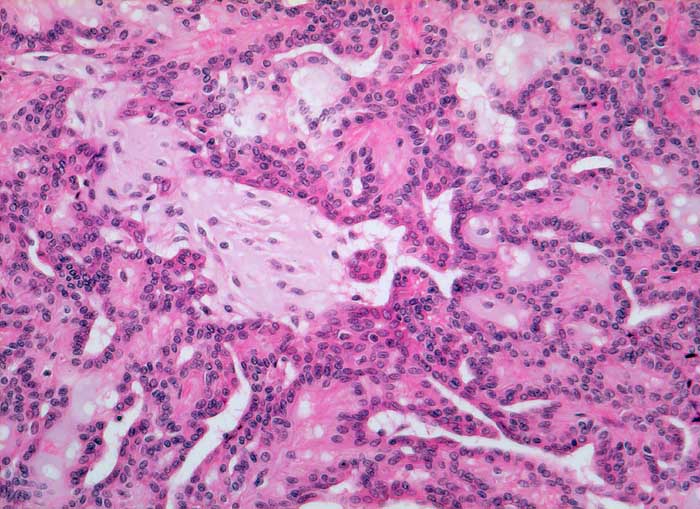

PathoPic ID 5443 - pleomorphes Adenom

pleomorphes Adenom

benigner Tumor

Parotis

Kopf & Hals, Sinnesorgane

Spindelförmige und ovale Zellen bilden drüsenartige Strukturen, die von reichlich Stroma umgeben sind. Kerne der Epithelzellen gleichförmig rundlich bis oval, ohne Atypien.

Histologie

160

53